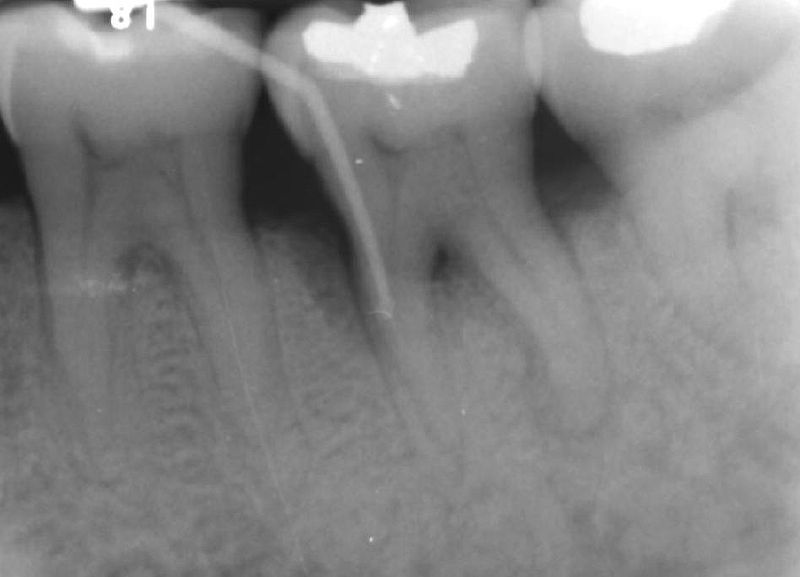

Image credit: Wikimedia Commons